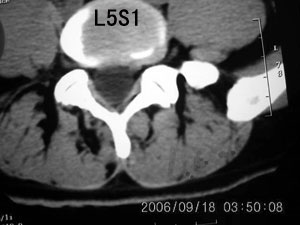

以下是引用守望可可西里在2006-9-18 21:29:00的发言:[br][br] 马尾肿瘤,密度较低,大部分似乎呈囊性变(看着很费眼),考虑室管膜瘤,建议mri。

以下是引用dyg在2006-9-18 22:27:00的发言:[br]正常脊髓.[br]分析:人的脊髓从枕大孔开始至腰1.2椎体为止,有2个生理膨大,分为颈膨大和腰膨大;该病人脊髓须然从腰段开始直至马尾似乎膨大,胆是与上段脊髓密度没有多大变化,所以我认为是正常膨大之延续;当然最好做ct增强或mri检查,排除肿瘤.

以下是引用飞虎在2006-9-18 20:18:00的发言:[br]部分椎管内密度不均且无ct值 故mri检查